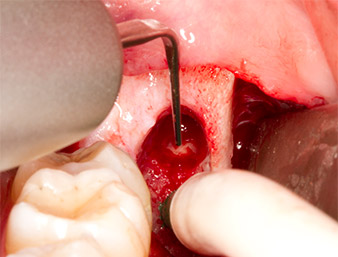

The tissue above the root remnant was not completely ossified and consisted for the most part of granulation tissue modified by inflammation (Fig. 4).

To obtain autogenous material for subsequent wound treatment, healthy bone chips were harvested from the surroundings of the root remnant with a piezo surgical instrument (Piezomed B5) (Fig. 5).